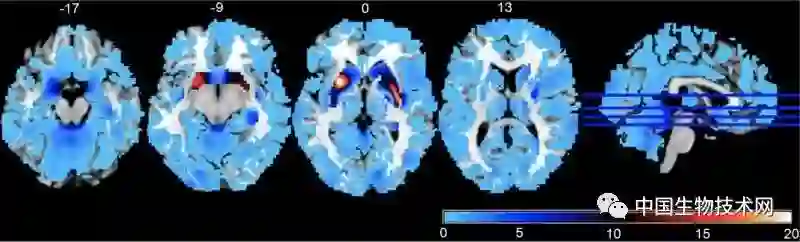

上图是精神分裂症的一个风险基因位点与全脑灰质体积关联性的3维空间分布;红色越深表示统计显著性越高,其次是黄色、绿色,统计显著性最低是蓝色。右图是最显著的脑区(壳核)灰质体积与全基因组变异位点关联性的曼哈顿图。结果按照染色体序号排列。

大脑截面图,蓝色表示和风险位点的相关性不显著,红色表示显著